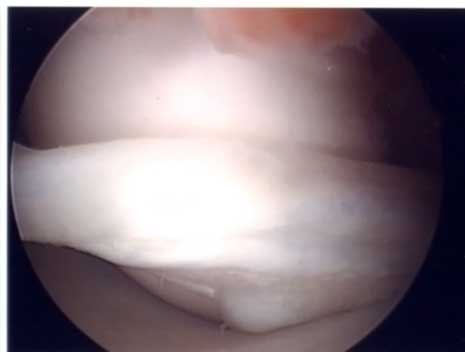

半月板部分切除術

半月板の手術は関節鏡下部分切除術が中心です。関節鏡を入れる1cm弱の傷と半月板を切除するパンチを挿入する別の1cm弱の傷の2カ所でほとんど出来ます。手術翌日に松葉杖なしで退院出来ます。関節鏡下部分切除術317例の10年以上の調査でも中高齢者の変性断裂は症状が続く場合には手術的に治されることがベターです。手術成績に影響する因子として、35歳以上の年齢、軟骨変性所見、半月後方1/3切除例、半月rim切除例などを指摘する論文もあります(Chantain 2001)。従来は後節1/3を切除することが多かったのですが、できるだけ痛みに関係する部分のみ切除する小部分切除法 (limited small resection) を現在では行っています。

(水平断裂合併)

(水平断裂は僅かに残存)

正常に見えるが